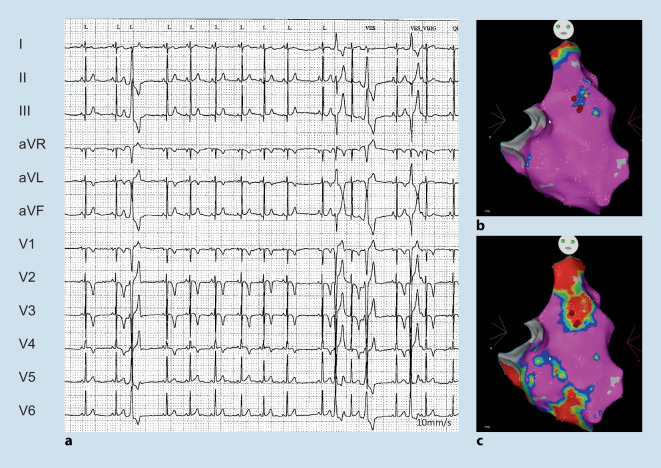

The overall prevalence of ARVC is around 0.08%. Many patients initially present with ECG abnormalities and VA. Of note, cardiac sarcoidosis may be an important phenocopy ([18–20]; Fig. 3). In addition, in up to 20% of patients with acute myocarditis ARVC is diagnosed [1]. Characteristic ECG findings include T wave inversion in V1–V3 with terminal activation delay often combined with atypical right bundle branch block ([19, 72]; Fig. 6). Ventricular extrasystoles (VEs) and/or VT with left bundle branch block (LBBB) morphology (with a superior axis) are a hallmark and must be distinguished from idiopathic RVOT VEs/VT with LBBB and inferior axis [5, 73]. AF is also relatively common with a prevalence around 9–30%. Rhythm control is preferred in the case of symptoms and/or heart failure/LV dysfunction [1].

Fig. 6.

A 21-year-old female competitive athlete who presented with a syncope while playing handball. The electrocardiogram (a) was already suspicious for arrhythmogenic right ventricular cardiomyopathy (right precordial negative T waves and VEs with superior and inferior axis). Please also note the unspecific signs of inferolateral early repolarisation. During programmed electrical stimulation, a sustained ventricular tachycardia (VT) with left bundle branch block inferior axis was inducible. Electroanatomic bipolar (color range 0.5–1.5 mV) (b) and unipolar (color range 5–8 mV) maps illustrate the predominately epicardial low voltage areas. The VT was successfully ablated from the endocardial anterior right ventricular outflow tract (c)